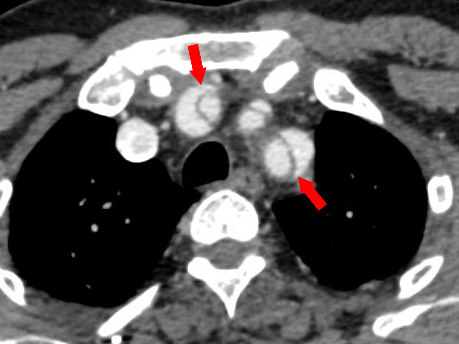

A large baseline aneurysm size, exceeding 7cm (Figure 12) and a rapid size progression of more than 10mm increase per year are associated with a higher risk for rupture.38,40,41 Additional CT findings that are predictors of aortic aneurysm instability include low thrombus-to-lumen ratio, luminal expansion with lysis of thrombus, “hyperattenuating crescent sign”, fissuration of thrombus, periaortic hemorrhage, a penetrating atherosclerotic ulcer, focal discontinuity of intimal calcification (Figure 13), and the “draped aorta sign.38,41 Correct documentation of any pleural effusion, pericardial effusion, or periaortic hematoma is a must as they are associated with increased risk of progression and mortality.42 Primary signs of aortic aneurysm rupture include retroperitoneal hematoma, periaortic fat stranding, and active extravasation of contrast material at the site of rupture.38,43

Figure 13 Axial CT angiography image in the delayed phase shows an aortic aneurysm (white asterisk) in the descending aorta with displaced intimal calcifications and a break in the rim of calcifications in its lateral aspect (red arrow). Focal discontinuity of intimal calcification is a predictor of aortic aneurysm instability.